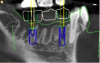

Co-diagnostic software was also used. While this type of software is available to practitioners from multiple manufacturers, in this case the laboratory provided the software. Co-diagnostic software allows for a prosthetically driven implant placement. In other words, the restorative outcome is taken into account prior to planning the placement of the implant. The software enables the team to incorporate the scanned image of the arch and the CBCT data to plan the surgery and fabricate a surgical stent, if so desired.12

This software allows accurate visualization of anatomic structures that are to be avoided during placement. This was especially important in this case because of the close proximity of the inferior alveolar nerve to the proposed implant sites. This planning has been found to lead to optimal results and allows the surgeon to place implants safely and efficiently.13-15

Once the scan and CBCT were loaded into the software, the respective files were merged to create a new image (Figure 2 through Figure 5). The data was then analyzed. The available software has vast libraries, some with up to 3,000 implant components from which to choose, from various manufacturers.12 The appropriate anterior-posterior position was determined, followed by the proper diameter and length of the implant bodies. This was all determined with the restoration in mind. The data was then used to fabricate a guide for the surgeon to use (Figure 6). These decisions were all made collectively by the team.